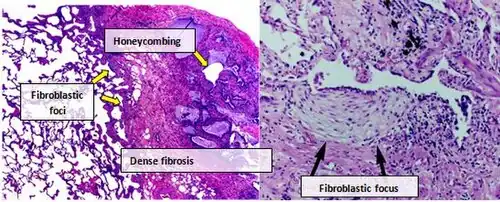

Histologia

O tecido pulmonar de pessoas com FPI geralmente apresenta um padrão histopatológico característico de PIU e, portanto, é a contraparte patológica da FPI.[3] Embora um diagnóstico patológico de PIU geralmente corresponda a um diagnóstico clínico de FPI, um padrão histológico de PIU também pode ser observado em outras doenças e na fibrose de origem conhecida (doenças reumáticas, por exemplo).[1][3] Há quatro características principais da PIU, incluindo fibrose intersticial em um "padrão de retalhos", cicatrizes intersticiais, alterações em favo de mel e focos de fibroblastos.

Os focos fibroblásticos são coleções densas de miofibroblastos e tecido cicatricial e, juntamente com a formação de favos de mel, são os principais achados patológicos que permitem o diagnóstico de PIU.